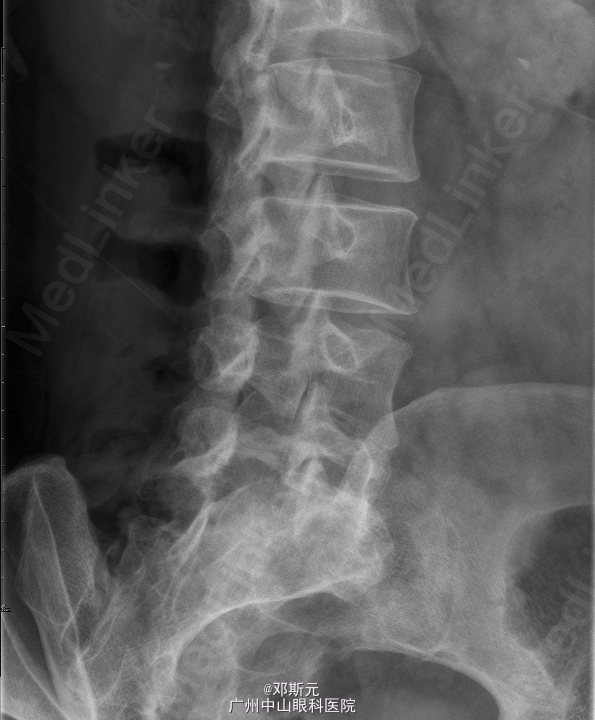

患者,女,47岁,主因“反复腰痛伴双下肢痛3月,加重20天”入院。 患者3月前无明显诱因出现反复出现腰痛,伴右下肢麻痛,以股外侧明显,疼痛影响活动,步行百米后便需要休息,休息后可自行缓解,左侧不明显,外院行理疗治疗后缓解。20天前无明显诱因下出现腰痛伴左下肢麻痛,右侧麻痛不明显,遂到外医院查MRI见腰4椎体滑脱,后为作进一步治疗到我院求医,门诊拟“腰椎滑脱症”收入我科。

查体:腰椎活动受限,双侧屈曲激发下肢放射性麻痹,腰4棘突叩击诱发左下肢麻痹,椎体棘突局部无压痛叩痛,左臀、左大腿外侧感觉稍差,余无异常。 辅助检查:外院腰椎MRI见:腰4椎体滑脱,L2/3至L5/S1椎间盘突出,L4/5椎间盘突出伴髓核脱出。L5/1椎间盘邻近椎体终板炎可能。腰椎退性变。

诊断:腰椎滑脱症(L4);腰椎间盘脱出症(L4/5);腰椎间盘突出(L2/3、L3/4、L5/S1)。术前检查未见明显异常,全麻下行“腰椎滑脱复位、椎间盘切除、椎弓根螺钉内固定、植骨融合术”。